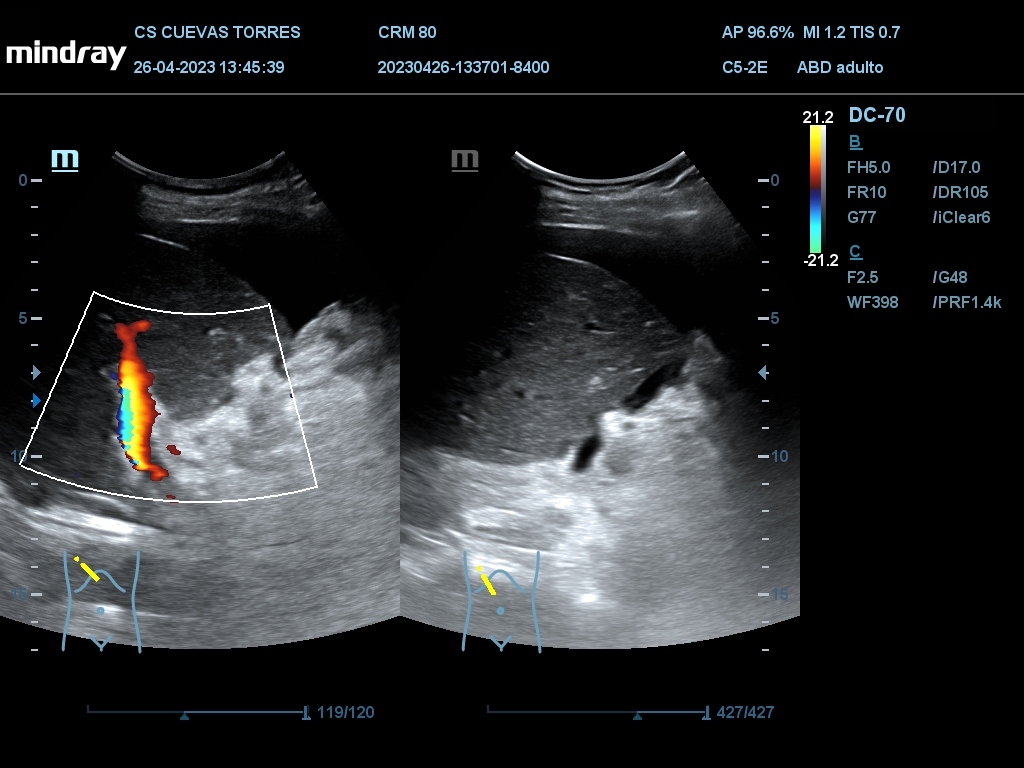

En la ecografía clínica observamos claramente la presencia de líquido libre desde el comienzo de la exploración. Continuando con el estudio Visualizamos circulación portal turbulenta y en el rastreo hepático una lesión ocupante de espacio (LOE) con captación Doppler de 7,45 cm de diámetro máximo.